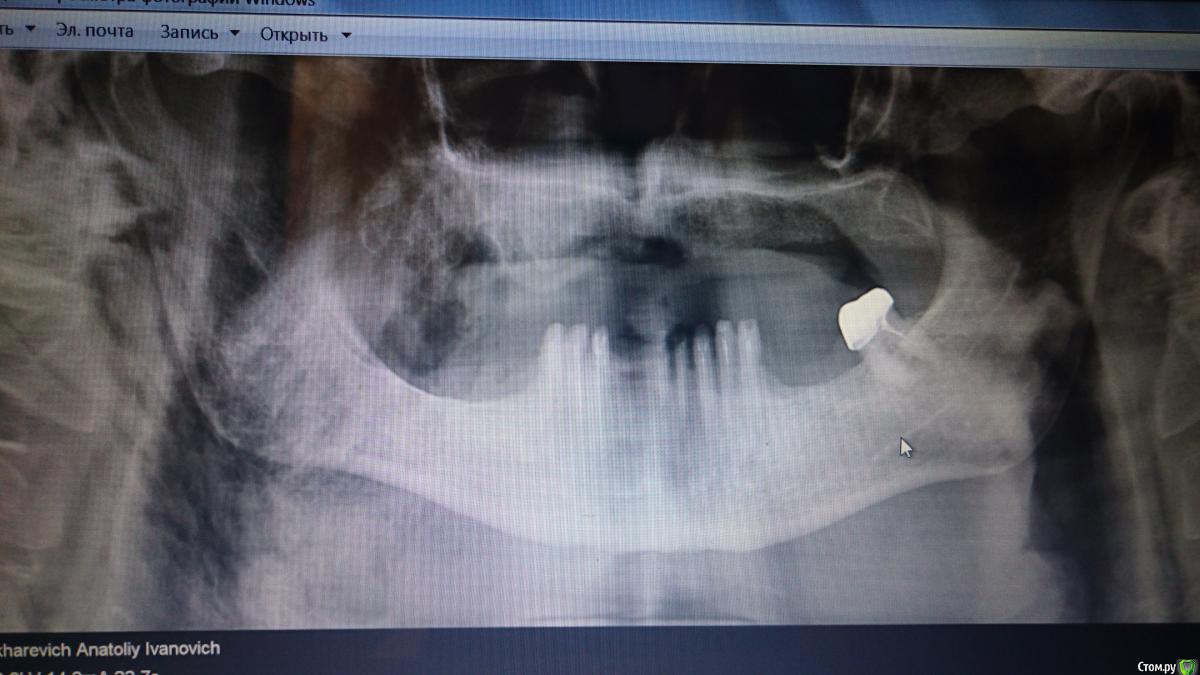

vadyasti Опубликовано 6 января, 2018 Поделиться Опубликовано 6 января, 2018 (изменено) Коллеги, что скажите по поводу снимка? Изменено 6 января, 2018 пользователем vadyasti Ссылка на комментарий

kramer Опубликовано 9 января, 2018 Поделиться Опубликовано 9 января, 2018 Я бы сказал саркома, причем с вовлечением уже мягких тканей Ссылка на комментарий

Дмитрий Л. Опубликовано 9 января, 2018 Поделиться Опубликовано 9 января, 2018 Снимок малоинормативен и необходимо сделать кт лицевого черепа. Ссылка на комментарий

vadyasti Опубликовано 9 января, 2018 Автор Поделиться Опубликовано 9 января, 2018 Есть кт в/ч.но там только в области бура справа есть изменения. Соглашусь с коллегой, что там и мягкие ткани затронуты. Завтра постараюсь узнать DS. у пациента. Направление давал в институт Герцена. Ссылка на комментарий

vadyasti Опубликовано 16 января, 2018 Автор Поделиться Опубликовано 16 января, 2018 На удивление, ничего паталогического в Герцена не обнаружили. Вот так вот. Ссылка на комментарий

___49___ Опубликовано 17 января, 2018 Поделиться Опубликовано 17 января, 2018 Артефакт на 1\4 снимка ? Ссылка на комментарий